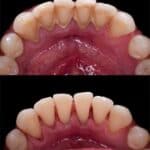

CLEANING

Preventative Hygiene care to remove surface stains, plaque, and tartar with specialized instruments.